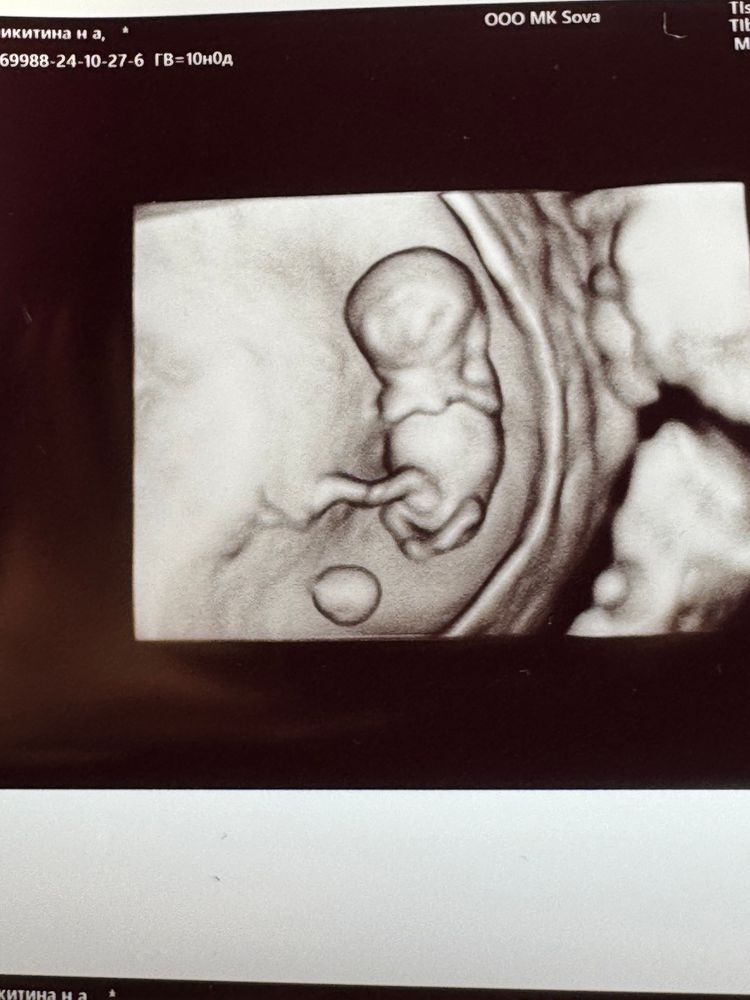

🥰какой интересный) Пузожитель) 🤗